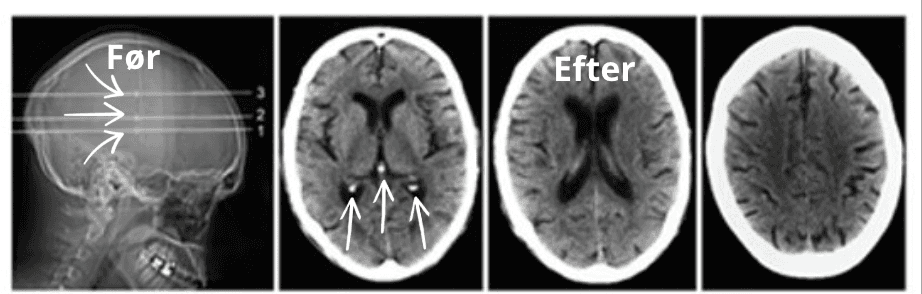

Den Gradvist Mulige Opløsning af Mikroskopisk Kalk i Hjernens Neurosystem - ofte synlig som Øget Tendens til Skum i Urinen gennem “Tissefasen” med Højnet “Kalk-markør”